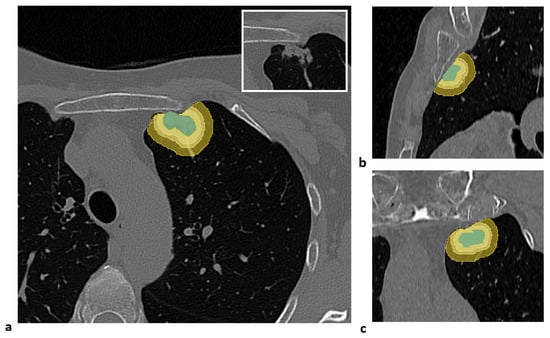

An example of a segmented lesion and the corresponding peritumoral regions is shown in Figure 1.

Figure 1. Example of lesion segmentation and the corresponding peritumoral regions generated by isotropic expansions of 3 mm, 5 mm, and 10 mm, constrained within the lung parenchyma mask, shown in the axial (a), sagittal (b), and coronal (c) views. The lesion is shown in the box at the top right of panel (a).